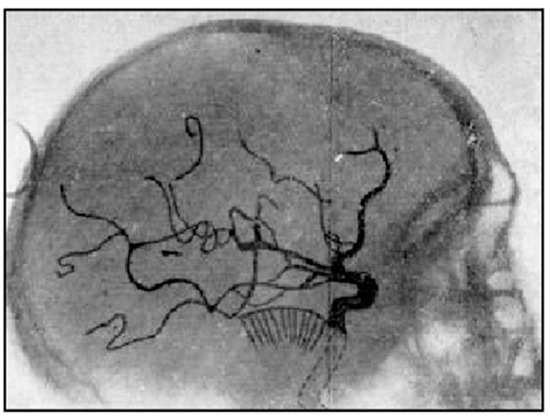

Another method of creating contrast in radiographs of the brain was to inject sodium iodinate into the cerebral arteries and so create contrast between large vessels and the surrounding tissues as demonstrated by Egas Moniz in 1927 [4] and shown in Figure 4. The technique was called angiography. Obstruction of vessels, displacement of these and development of new vessels could be seen and were used in the diagnosis of disease.

Figure 4.

Positive radiograph of the head after arterial injection of sodium iothalamate, lateral view (1927). The sodium iothalamate is seen in larger arteries. It has a low signal, creating contrast between the arteries and the surrounding brain.